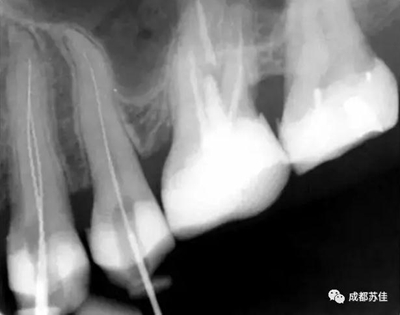

空間分辨率最高可達(dá)16.7lp/mm,16位(65,636)的灰度,能夠可靠的分辨出D1級(jí)別的齲損及細(xì)小至ISO 06 級(jí)別的根管器械。